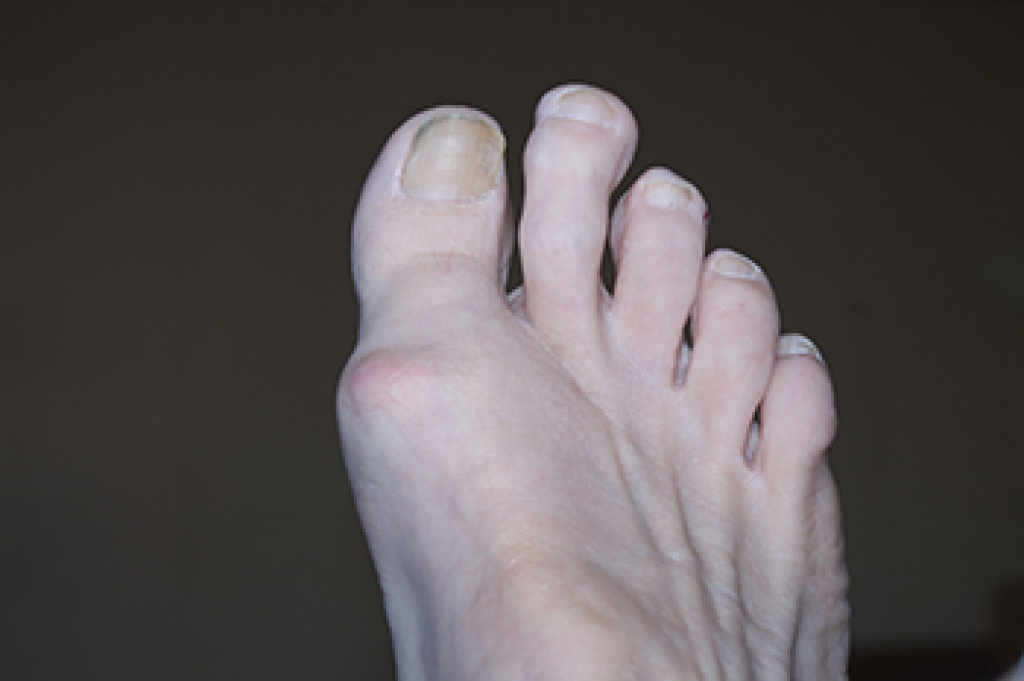

Morton’s toe, also known as Greek foot, is a condition where the second toe is longer than the big toe. While it is often a benign anatomical variation, it can lead to discomfort and pain due to altered foot mechanics. Individuals with Morton’s toe may experience metatarsalgia, which is pain in the ball of the foot, as well as calluses, bunions, and discomfort while walking or standing. Treatment typically begins with conservative measures, such as wearing supportive footwear, using orthotic inserts, and practicing foot stretches. However, if pain persists or worsens, it is important to consult a podiatrist. This type of doctor may recommend more advanced treatments, including targeted exercises or, in severe cases, surgery to alleviate pain and correct alignment issues. If you suspect you have Morton’s toe and are experiencing discomfort, it is suggested you schedule an appointment with a podiatrist for a thorough assessment and tailored treatment options.